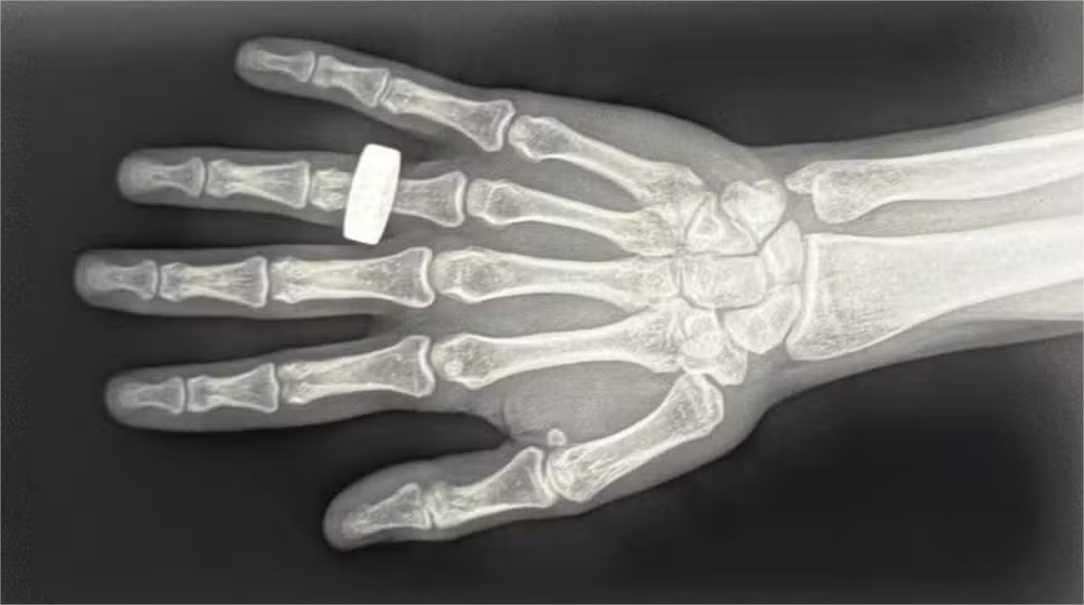

Em post no X (antigo Twitter), Chun Wang, comandante da missão, compartilhou uma das imagens capturadas a bordo da nave Dragon 207 “Resilience”. Trata-se de uma varredura em preto e branco de uma mão, com um anel em um dos dedos, tirada a mais de 320 km de distância do solo e uma velocidade de 28.163 km/h.